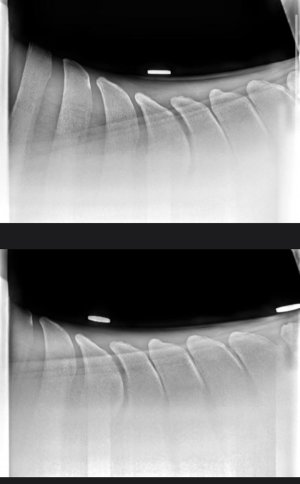

9 year old, 15.2 mare. She has been struggling with poor performance that has manifested in bucking, hollowness and reluctance to go forward. She started refusing fences which prompted a work up with her regular vet.

She was trotted up, lunged on hard and soft and had flexion tests. She was negative to all, with the exception of a very slight positive flexion on the hind limbs. Manipulation of the back was unremarkable.

Vets advised that x-rays revealed three very narrow interspinal spaces along the thoracic spine. These were medicated with a corticosteroid.

I would be interested to hear what others think of these radiographs and course of treatment? I feel like medicating is simply masking a problem that will still be present and symptoms will eventually return when the medication loses efficacy?